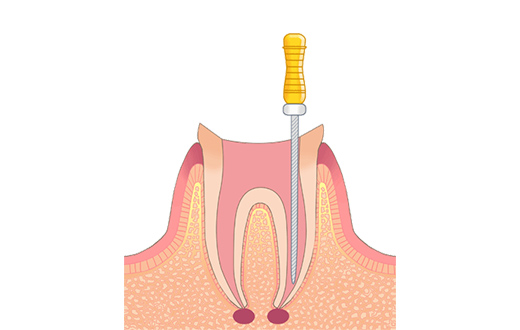

STEP02抜髄・感染根管処置

歯の中の歯髄を取り除きます。これを抜髄と言います。既に根の治療がされている歯が再感染を起こし、炎症がある場合や、歯髄が既に死んでしまっている状態の場合は感染根管処置と言い、中に入っている感染が疑われる物質を取り除きます。

-

STEP03根管洗浄・貼薬

根の中を洗浄・消毒し、お薬を入れます。このステップを何度か繰り返すことで、根の中がきれいになっていきます。

もともとの虫歯の大きさや、炎症の度合いによっては、この治療の回数が増えてしまうこともあります。歯の周囲の炎症がなくなるまで続けます。 -